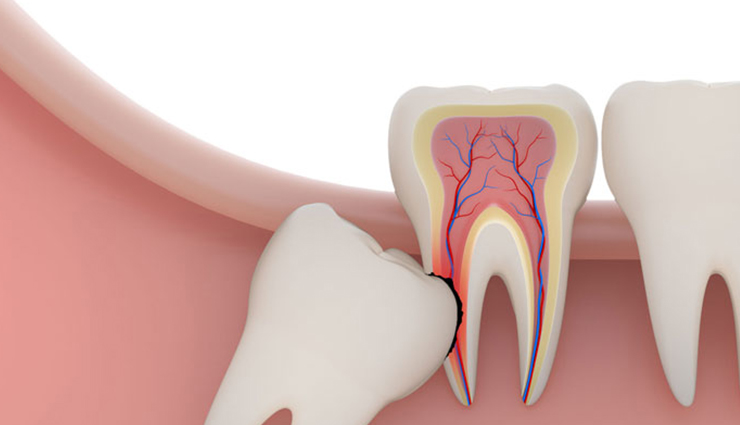

آیا باید دندان عقل را بکشیم؟ دندان عقل و هرآنچه که باید درباره آن بدانید

دندان عقل، سومین و آخرین دسته از دندانهای آسیاب است که در اواخر نوجوانی یا اوایل بیستسالگی پدیدار میشود. اگر این دندانها بدونانحراف و سالم باشند، همانند دیگر دندانها ارزشمند خواهند بود، اما در بیشتر مواقع این طور نیست و باید به فکر کشیدنشان بود. با این تفاسیر این سؤال پیش میآید که علت درآمدن دندانی که به کشیدن نیاز پیدا خواهد کرد و بلااستفاده است چیست؟ در ادامهٔ این مقاله علاوه بر یافتن جواب این سؤال، اطلاعات دیگری هم دربارهٔ دندان عقل در اختیارتان قرار خواهیم داد. بخشی از مقاله هم به ارائهٔ توضیحاتی دربارهٔ روند کشیدن این دندان، دوران بهبودی و توصیهها و اطلاعاتی در این باره اختصاص دارد.